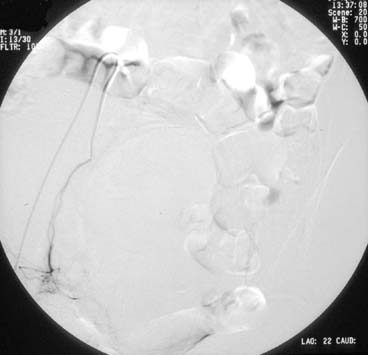

A pelvic arteriogram is generally performed to delineate the arterial anatomy. Embolization of the uterine artery contralateral to the access site is usually attempted first. A catheter is directed over the guidewire, up the external iliac artery, to the bifurcation of the abdominal aorta. Using a steerable guidewire, the catheter is directed down the common iliac artery and then down the hypogastric artery and into the origin of the uterine artery. Angiography is used to aid in guiding the catheter into the proper position (see Figs. 1 and 2). Embolic material is mixed with contrast material and injected. Repeat injections continue until blood flow significantly slows or stops (see Fig. 3). The catheter is then withdrawn and the procedure repeated on the ipsilateral uterine artery (see Fig. 4).

Fig. 1. Right internal and external iliac artery with uterine artery noted in inferior field.

Fig. 2. Right uterine artery with uterine vasculature beginning to fill.